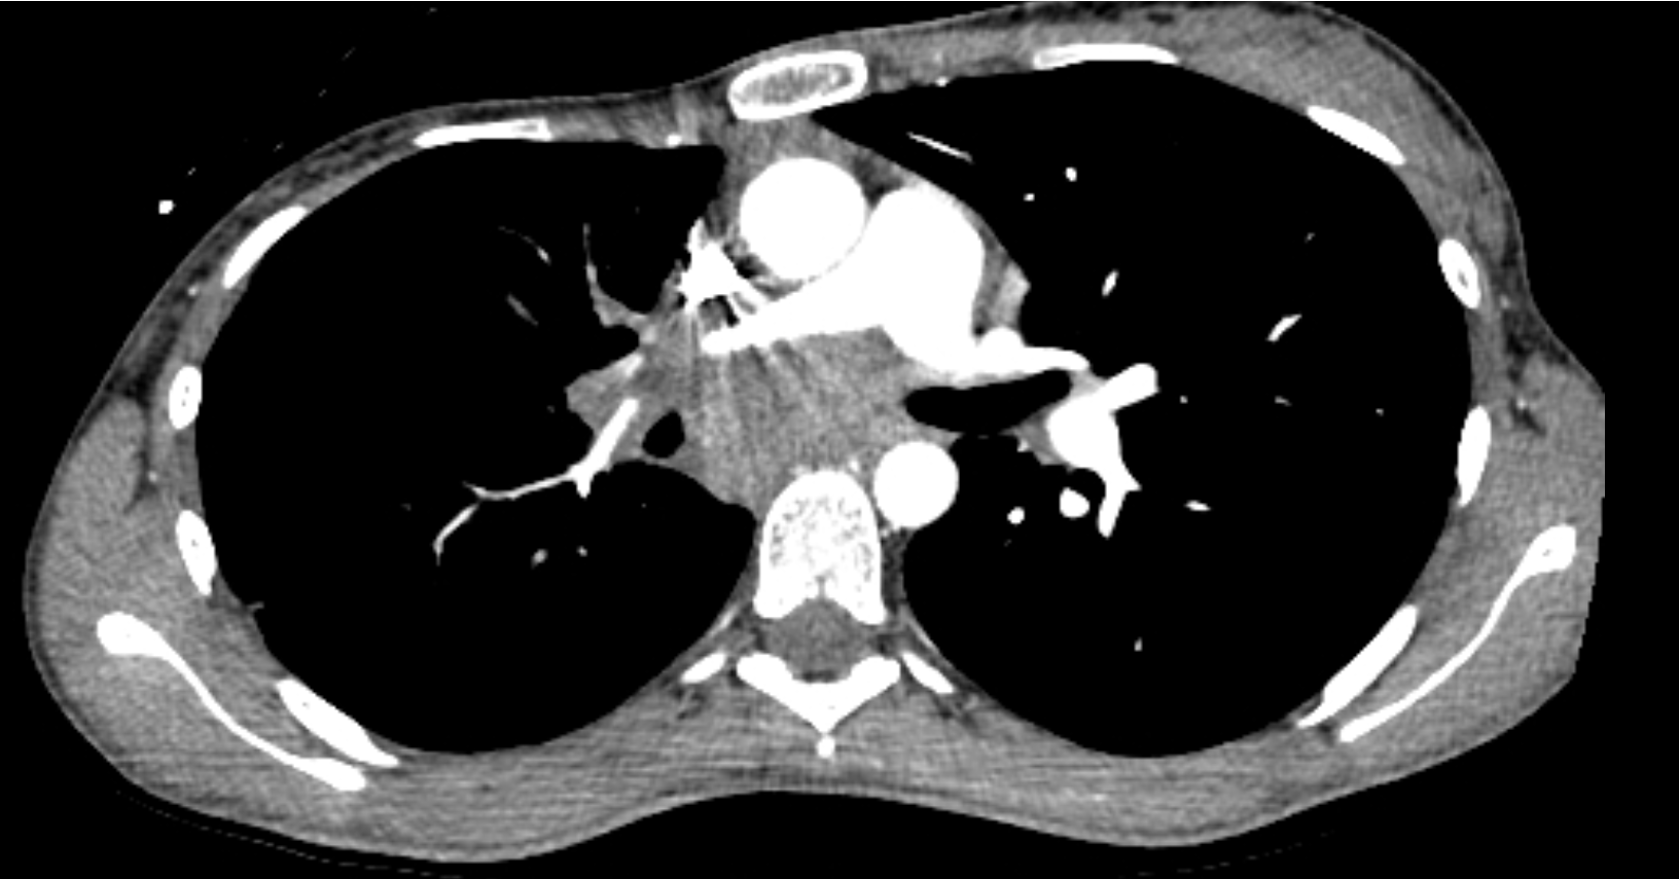

Case Presentation: A 22-year-old woman presented after an episode of syncope and chest pain. The patient reported weight loss and anorexia for 2 weeks and fever, fatigue, and chills for a few days prior to presentation. She had recently moved to Georgia from Missouri. She had no significant medical or family history. Initial workup showed a 4.5 cm sub-carinal mass encasing the pulmonary artery and causing pulmonary stenosis. Initial echocardiogram was normal, but she subsequently developed a moderate pericardial effusion during the next few weeks. Bronchoscopy with endobronchial biopsy (EBUS) was performed twice in addition to video-assisted thoracoscopic surgery with mediastinal biopsy of the mass and surrounding lymph nodes. Pathologic examination revealed necrotizing granulomatous inflammation with negative bacterial, fungal, AFB cultures, and negative cytology and flow cytometry.During the second bronchoscopy with EBUS, the patient was given 4 mg of dexamethasone pre-procedurally. Clinical improvement was noted for the next 24-48 hours. We hypothesized that dexamethasone decreased immune activation after suspected infection with histoplasmosis given her previous residence in Missouri. Itraconazole and prednisone were initiated to empirically treat for histoplasmosis. Around the time of treatment initiation, a urinalysis showed proteinuria and microscopic hematuria. Rheumatologic workup resulted cytoplasmic-antineutrophil cytoplasmic antibody (C-ANCA) positive with immunofixation titers of 1:320, serine proteinase 3 markedly positive at 640, and rheumatoid factor >200. Urinary sediment under phase contrast microscopy showed many red blood cells (RBC); 60% had dysmorphic features. During her hospital stay, the patient developed dermatologic manifestations including delayed pressure urticaria of the extremities that resolved with steroids and intermittent vasculitic rash in the lower extremities. With evidence of glomerulonephritis, vasculitic rash, and serologies positive for C-ANCA and serine proteinase-3 in the setting of necrotizing granulomatous inflammation, a primary diagnosis of GPA was made. Histoplasmosis with subsequent immune activation was considered in the diagnostic process, but GPA was favored as a diagnosis considering positive serologic testing and multiorgan manifestations. Itraconazole was discontinued with initiation of pulse dose steroids and rituximab. There was clinical improvement with initial steroid treatment including resolution of pericardial effusion as well as improvement of generalized symptoms. Subsequent evaluation of glomerulonephritis and mediastinal mass were planned for the outpatient setting.

Discussion: Granulomatosis with polyangiitis (GPA) is a C-ANCA necrotizing vasculitis with non-specific presenting clinical features of GPA commonly involving the sinuses, urinary tract, joints, and skin. Our 22-year-old female patient, who initially presented with a sub-carinal mass, had an unusual presentation of GPA. Previous cases of GPA have associations with necrotizing granulomatous masses. This is the first case we found to have GPA present as a sub-carinal mass with necrotizing granulomatous inflammation; subsequent imaging of the sub-carinal mass following treatment would be of particular interest.